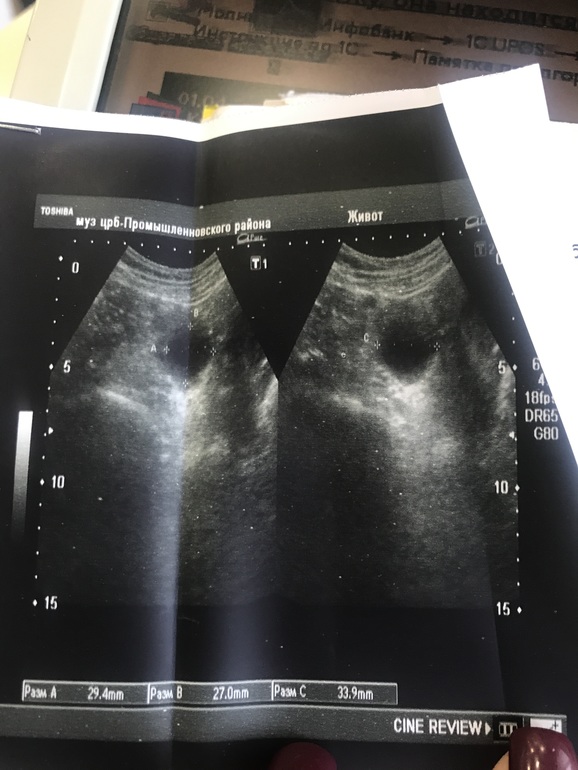

Фолликулярная киста на узи

2 сентября вместо месячных один день была коричневая мазня,признаки беременности есть ,вчера тянуло поясницу .Пошла на узи,врач молоденькая ,говорит беременности нет ,но есть фолликулярная киста правого яичника ,в июле была на узи ,кисты не было ,а сейчас размеры 29*27*33 причём не маленькие ,сделала утром тест есть бледная полоска ,было у кого-нибудь так ?очень хочу малыша